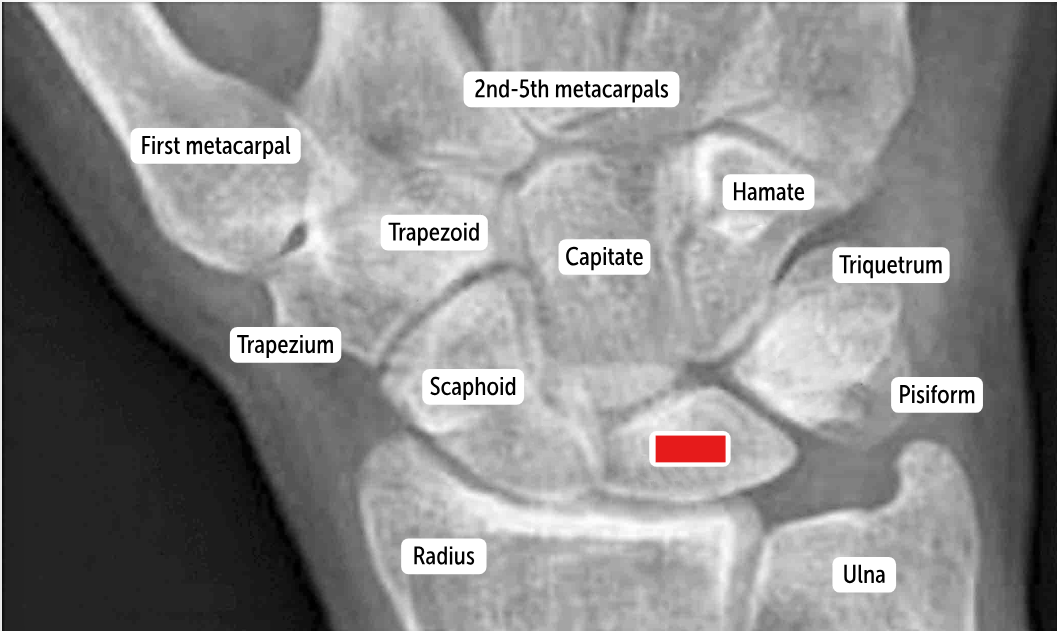

The most commonly fractured carpal bone by falling on an outstretched hand, which has a risk of avascular necrosis, is the __________.

Scaphoid bone

The most commonly dislocated bone after a fall on an outstretched hand is the ___________.

Lunate bone

Carpal bones by row:

So Long To Pinky, Here Comes The Thumb

Scaphoid, Lunate, Triquetrum, Pisiform, Hamate, Capitate, Trapezoid, Trapezium

Scaphoid

Lunate

Triquetrum

Pisiform

Hamate

Capitate

Trapezoid

Trapezium